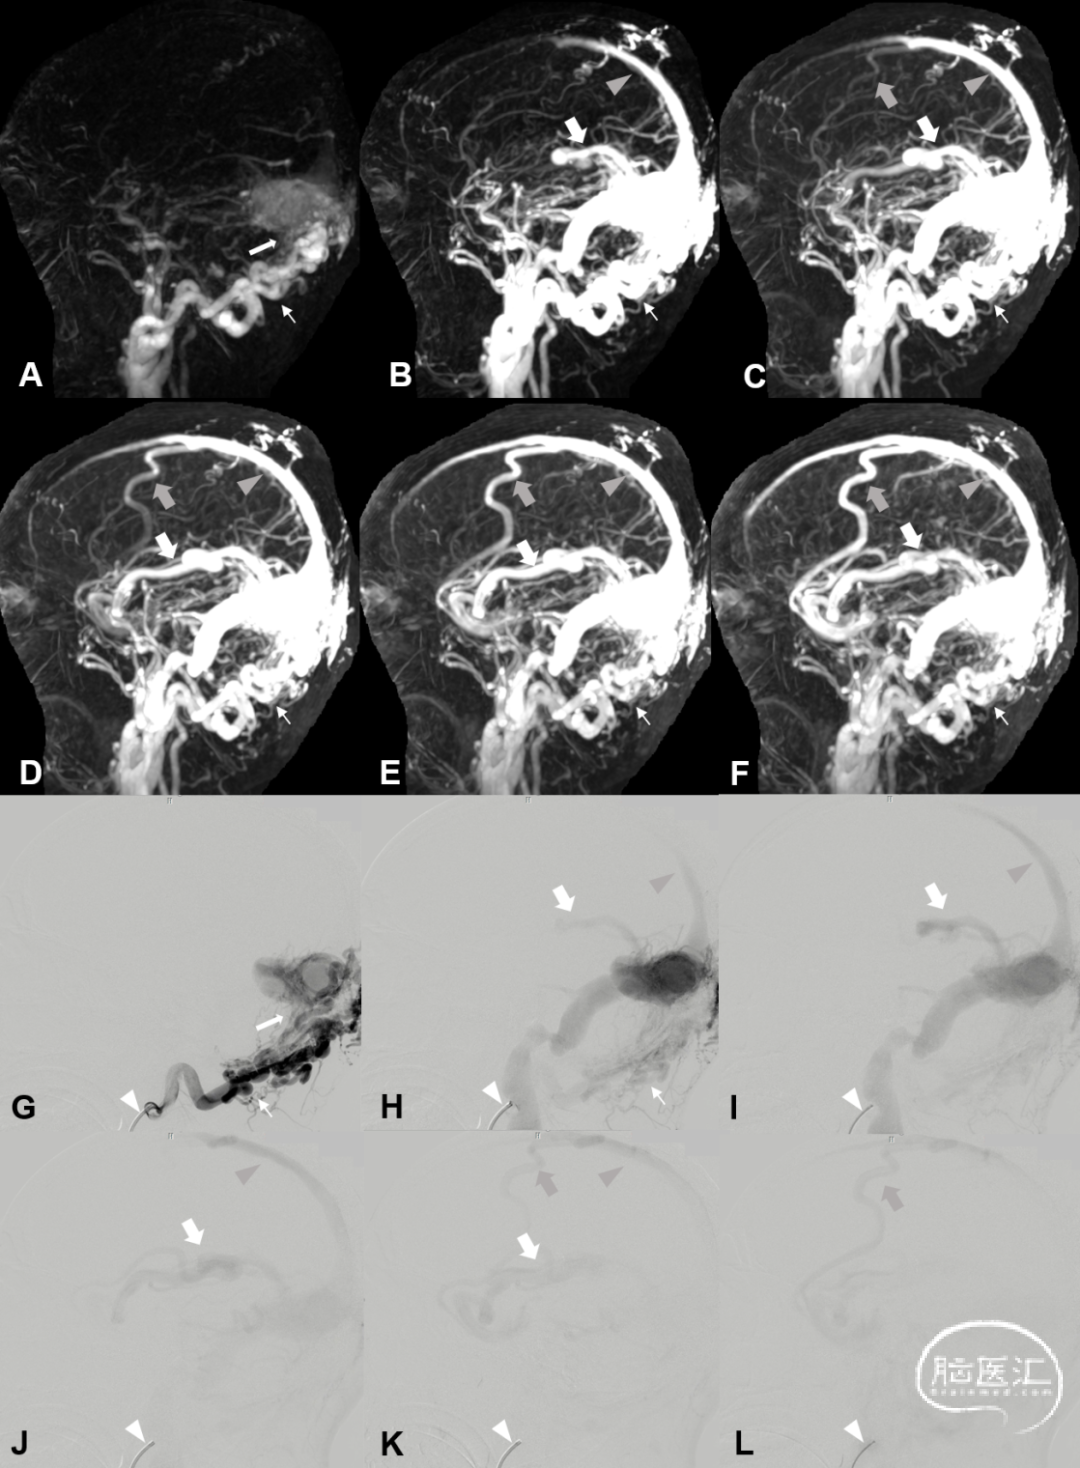

动态增强MRA (Dynamic contrast enhanced, DCE-MRA) 可以提供良好的时间分辨率,识别颅内血流动力学,协助DAVF的Borden或Cognard分型。静脉引流方向可预测颅内出血 (ICH) 及非出血性神经功能缺损 (NHND) 的风险。有学者进行了DCE-MRA与DSA对比,结果表明DCE-MRA可以对DAVF进行诊断和识别静脉引流方向,可以作为术前的初步判断DAVF静脉引流的工具。DCE-MRA可识别供血动脉、瘘口位置及引流静脉,同时给出全颅血流动力学特征,是在评估DAVF有无侵袭性倾向的无创检查手段。

图9. 硬脑膜动静脉瘘定位。DCE-MRA示上矢状窦区桥静脉型DAVF (A白箭) ,超选择颈外动脉及枕动脉造影证实DAVF位于上矢状窦区桥静脉 (B、C白箭) 。DCE-MRA检查发现上矢状窦区桥静脉上的低流量DAVF (D白箭) ,颈外动脉造影证实DAVF位于上矢状窦区桥静脉 (E、F白箭) 。

图10. 硬脑膜动静脉瘘分型:Cognard IIa+b级DAVF患者颅脑DCE-MRA及DSA图像。DCE-MRA发现右侧横-乙状窦区DAVF (A-F, 每帧图像的时间间隔为2s) ,主要供血动脉为右侧枕动脉 (细箭) 。DAVF发生在右侧横-乙状窦区 (A白箭) ,伴有上矢状窦逆流 (B-F灰箭头) 、Trolard静脉 (C-F灰箭) 和Labbe静脉 (B-F白箭) 逆流。DSA (G-L,每帧的间隔时间为2秒) 证实右侧横-乙状窦区DAVF。导管 (G-L白箭头) 置于右侧枕动脉 (G、H细箭) 。DAVF发生在右侧横-乙状窦区 (G白箭) ,伴有上矢状窦逆流 (H-K灰箭头) ,Trolard静脉 (K、L灰箭) 和Labbe静脉 (H-K白箭) 逆流。